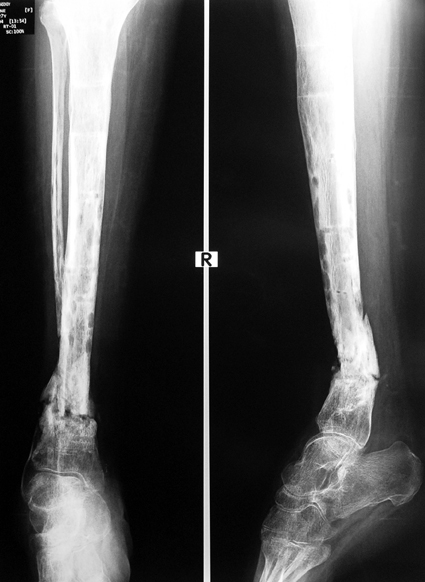

Pseudarthrosis of fracture and pseudarthrosis treatment is currently important problem for orthopedic surgery. Various treatment modalities have been described for pseudarthrosis treatment. All of the treatment methods include high complication rates and additional problems. Leg-length discrepancy, deformity and soft-tissue loss and chronic infection can concomitance with pseudarthrosis. Many internal or external fixation techniques have been described for pseudarthrosis.

Debridement and resection of bone fragment from the pseudarhtosis area vascularized or nonvascularized fibula graft, vascularized muscle flaps, bone grafting followed internal fixation techniques make a option for treatment of pseudarthrosis treatment. But these treatment modalities may not correct deformity and leg-length discrepancy.

Recently, ilizarov techniques which is basis depend on distraction osteogenesis , bone segment transport or acute shortening after the resection at the site of pseudarthrosis combined with lengthening at another level of bone have been used. These treatment techniques may include some advantage for problems of infection, leg-length discrepancy, soft-tissue loss, and joint contracture.